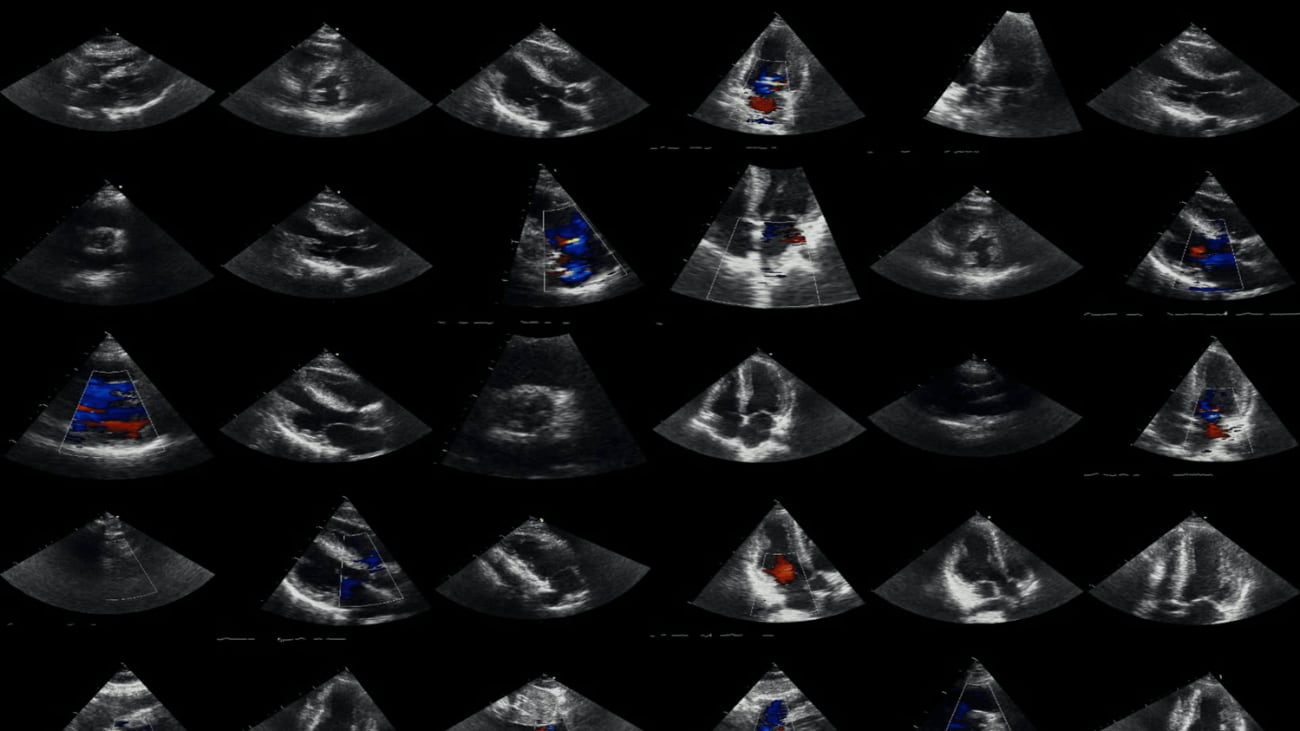

UCSF-led research with deep neural networks enhances echocardiogram views of major cardiac conditions.

Most standard echocardiograms provide two-dimensional visual images (2D) of the three-dimensional (3D) cardiac anatomy. These echocardiograms often capture hundreds of 2D slices or views of a beating heart that can enable physicians to make clinical assessments about the function and structure of the heart.

To improve diagnostic accuracy of cardiac conditions, researchers from UC San Francisco set out to determine whether deep neural networks (DNNs), a type of AI algorithm, could be re-designed to better capture complex 3D anatomy and physiology from multiple imaging views simultaneously. They developed a new “multiview” DNN architecture to enable it to draw information from multiple imaging views at once, rather than the current approach of using only a single view. The researchers then trained demonstration DNNs using this architecture to detect disease states for three cardiovascular conditions: left and right ventricular abnormalities, diastolic dysfunction, and valvular regurgitation.